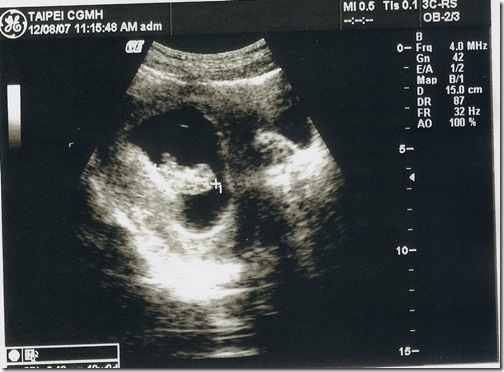

這次的超音波就不用畫圖說故事了吧 !!

再看不懂就只能說.. 你是火星來的嗎